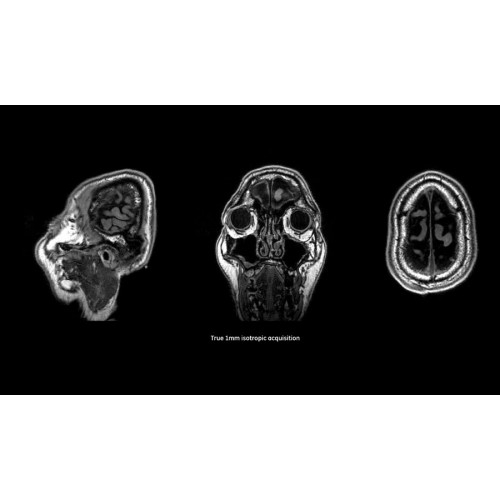

Система SIGNA Pioneer воплощает поразительные достижения в области визуализации. Передовая технология Total Digital Imaging (TDI) позволяет добиться большей четкости изображений и на четверть повысить соотношение сигнал/шум.

• Технология Digital Surround Technology (DST) — это новая технология объемной оцифровки данных, объединяющая сигналы от каждого элемента катушки. Прекрасное соотношение сигнал/шум и чувствительность поверхностных катушек в сочетании с превосходной однородностью и высокой проникающей способностью встроенной радиочастотной катушки — все это позволяет создавать качественные изображения не только позвоночника, но и всего тела.

Помимо технологии 97 РЧ-каналов, SIGNA Pioneer использует магнит 3.0Т высокой однородности, предназначенный для повышения качества визуализации во всех областях, а также закладывающий прочный фундамент для долгосрочных инвестиций и роста клинических возможностей.